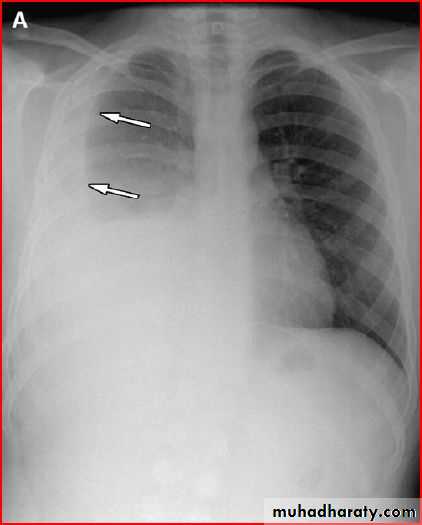

3 month infant presented with cough & dyspnea

Xray shows hyperinflated chest (depresed diaphragm , > 6 ribsMay be bronchiolitis

Hyperinflated chest

Hx of FB

A showing normal x rayB xray during expiration showing lt. lung emphysema make shifting of mediastinum